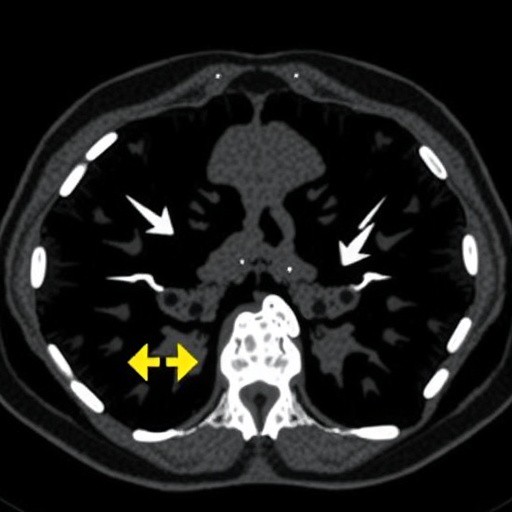

Bone metastases occur when malignant cells from a primary tumor spread to the bone, disrupting normal bone physiology and causing pain, fractures, and significant morbidity. Clinicians rely heavily on imaging modalities such as CT scans to identify these lesions, yet the interpretation of metastatic involvement remains a complex task, often burdened by human error and variability. The newly developed AI system harnesses deep learning algorithms trained on vast datasets of CT images, enabling it to discern subtle radiographic features typical of bone metastases, even at early stages or in locations difficult to visualize. This capability holds promise for enhancing early detection, guiding treatment decisions, and ultimately improving patient outcomes.

One of the most compelling aspects of this AI tool is its ability to detect bone metastases from a spectrum of primary malignancies, including breast, lung, prostate, and renal cancers. This universality contrasts with prior models often tailored to single cancer types, representing a substantial stride towards comprehensive oncologic support. By accurately mapping the extent and distribution of metastatic burden, the system aids oncologists in staging disease, assessing treatment response, and stratifying patients for clinical trials or novel therapies.

Beyond detection, the system shows promise in characterizing metastatic lesions based on morphological features, potentially assisting in differentiating active tumors from healed or sclerotic lesions. Such nuanced differentiation could guide biopsy decisions and personalized treatment planning, an area where conventional imaging often falls short. The implications for patient management are profound, ranging from optimizing radiation therapy fields to monitoring emerging disease with unparalleled precision.